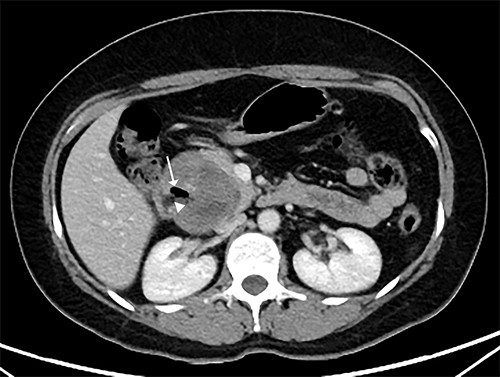

Our patient is a 44-year-old healthy female who presented to the emergency department with a 1-week history of epigastric pain associated with melena, fatigue and dizziness. The abdomen was soft without tenderness, and the laboratory test showed haemoglobin at 7.3 g/dL. After two units of red blood cell transfusion, she underwent an emergency endoscopy. A 2 cm bleeding ulcer was found in the duodenal bulb with jagged edges and an adherent clot (Fig. 1). Epinephrine injection and argon plasma coagulation were used to achieve haemostasis. A CT scan revealed a well-defined heterogeneous 6.7 cm mass with solid and cystic components arising from the head of the pancreas and the enhancement of contrast in the solid component (Fig. 2). No dilatation of the common bile duct or pancreatic duct was noted. The patient was discharged without signs of bleeding and haemoglobin at 10.4 g/dL. Biopsy samples of the duodenal ulcer showed chronic inflammation, and some glandular structures suspicious of neoplasia.

CT scan showing a well-defined heterogeneous 6.7 cm mass with solid and cystic components arising from the head of the pancreas with enhancement of contrast in the solid component, and some areas with active bleeding (white arrow). The tumour was in direct proximity to the duodenum.